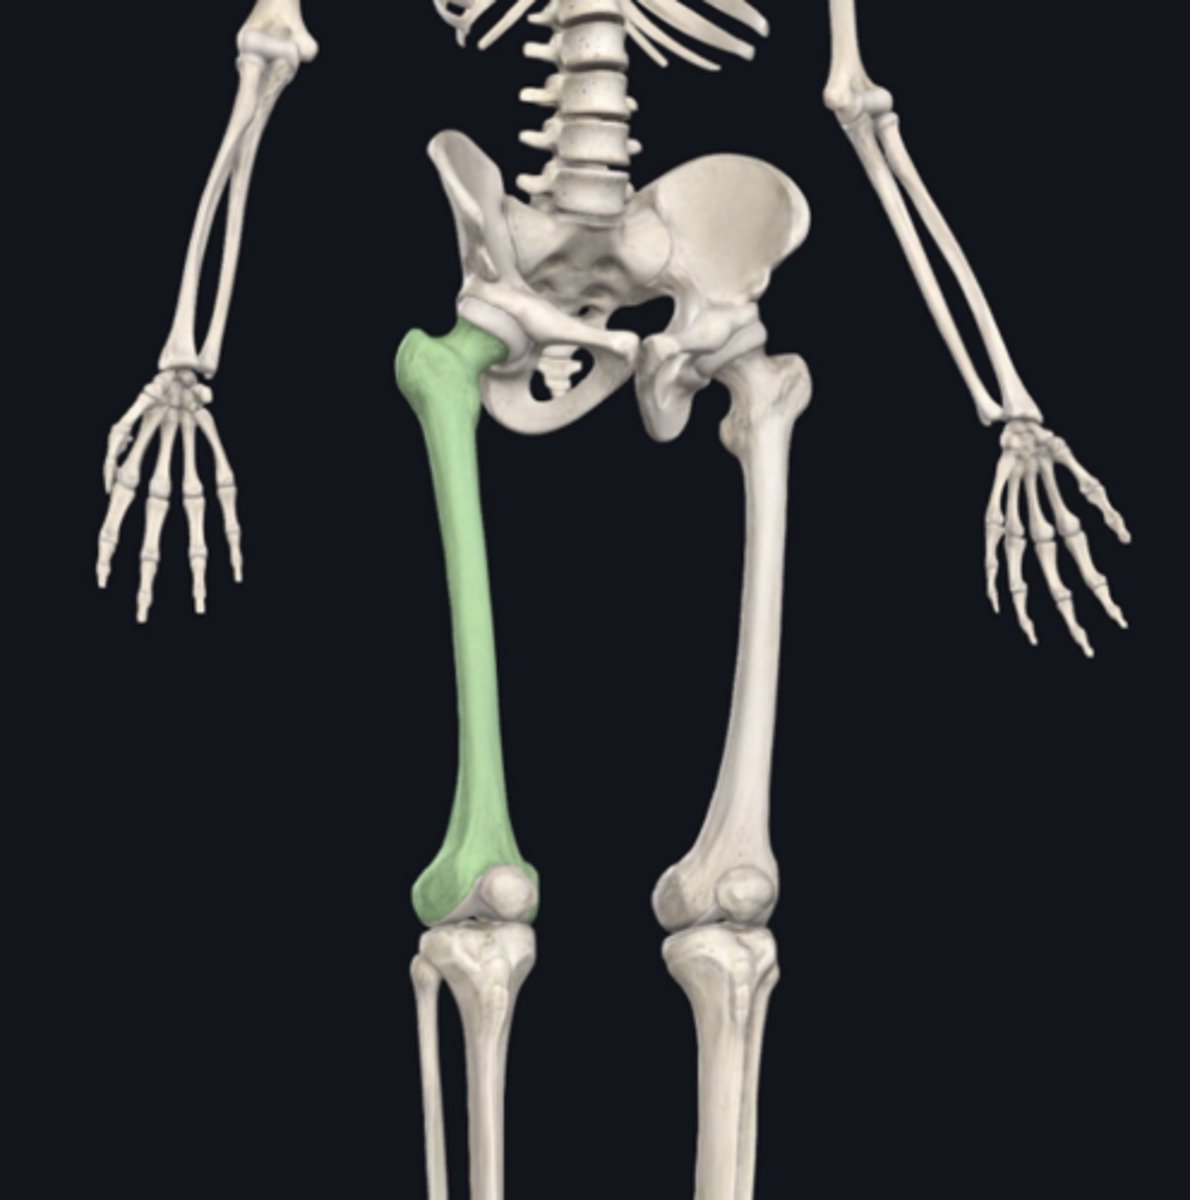

Femur

Identify the bone indicated in green. (Free response)